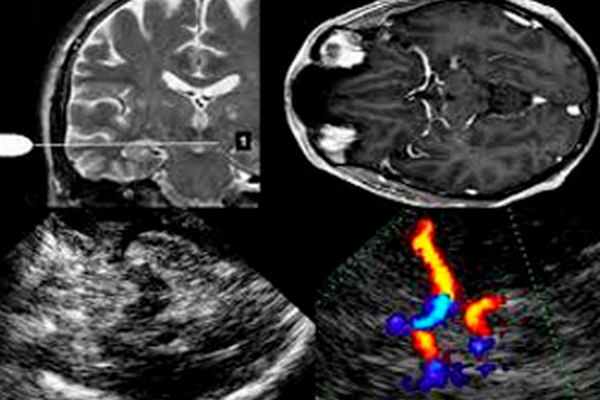

- Ультразвуковая допплерография или УЗДГ. Основывается на эффекте допплера, является самым простым и безопасным методом. Недостаток УЗДГ — невозможность исследовать артерии внутри черепа.

- Дуплексное сканирование. Это родственный УЗДГ метод, но более информативный, так как удается проверить сосуды в труднодоступных местах, в частности, внутри черепа. При дуплексном сканировании исследуется скорость и направление кровотока, а также толщина сосудистых стенок, наличие тромбов и т. д.

- Триплексное сканирование. Это дуплексное сканирование, дополненное цветовым картированием потока. Метод является самым информативным и позволяет с точностью оценить скорость кровотока и состояние сосудов, в том числе и у основания головного мозга.

Дуплексное сканирование артерий и вен — один из популярных методов ультразвуковой допплерографии, который позволяет получить информацию о состоянии кровотока в магистральных артериях и венах.

На основе дуплексного сканирования был создан еще один метод диагностики — это триплексное обследование. Это тоже самое дуплексное сканирование, но оно дополнено цветным допплеровским картированием. То есть возможности обычного дуплексного сканирования расширены за счет кодирования информации с помощью цвета.

Раньше УЗ-оборудование позволяло проводить исследование сосудов только «вслепую» - без визуализации самого сосуда, лишь по характеру кровотока в нем (используя эффект Допплера, определяли скорость и направление движения потока крови. Этот метод называется «УЗДГ» - «Ультразвуковая допплерография сосудов»).

В настоящее время метод УЗДГ самостоятельно не используется, он входит в состав более современного УЗ-обследования сосудов, которое называется «Дуплексное сканирование сосудов» (ДС сосудов). Некоторые доктора продолжают называть этот метод по-старому: « УЗДГ» . Поэтому существует путаница в названии этого метода УЗ-исследования сосудов.

Термин «Дуплексное сканирование сосудов» означает «двойное сканирование сосудов» и позволяет не только определить характер движения крови по сосудам, используя эффект Допплера (это и есть УЗДГ), но и детально рассмотреть сосуды: определить их размеры, строение сосудистой стенки (которая уплотняется и утолщается при атеросклерозе, утолщается при воспалении сосуда и т.д.); определить ход сосудов (который может быть ровным или извитым вплоть до «петлеобразного»), выявить внутрисосудистые образования – атеросклеротические бляшки, тромбы, создающие препятствие кровотоку.

Современные УЗ-аппараты добавляют к этим двум составляющим исследования, еще и возможность окрашивания сосудов цветом в зависимости от направления кровотока. Поэтому появился термин «Триплексное сканирование сосудов» (то есть тройное сканирование).

Термины «Дуплексное сканирование сосудов», «ДС сосудов», «Триплексное сканирование сосудов», «УЗДГ сосудов» означают одно - ультразвуковое исследование сосудов, которое на современных УЗ-аппаратах проводится в триплексном режиме.